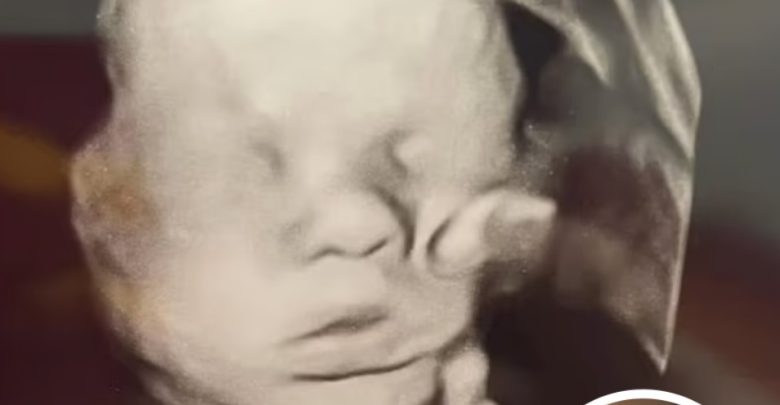

kentucky mother amanda foster, who faced past pregnancy loss, was surprised at a 32-week ultrasound when her baby’s hand appeared resting on his head, offering a moment of hope and relief.